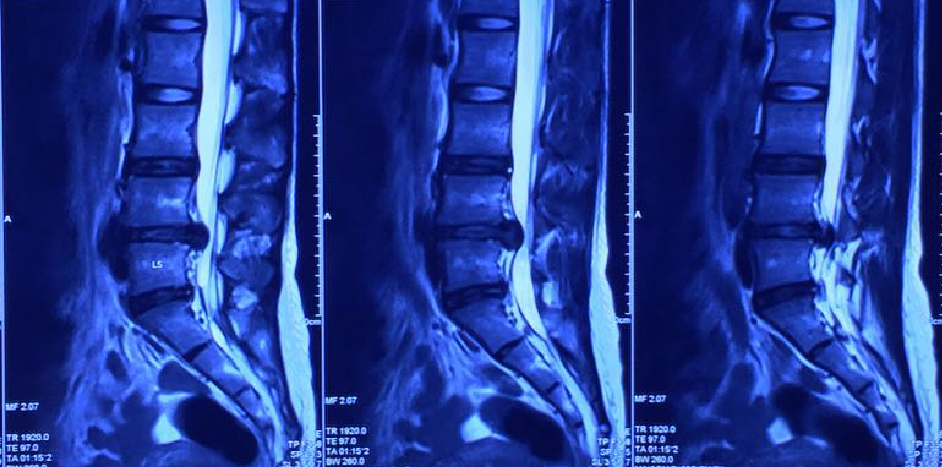

Illustrated MR 3, MR 4

In January 2016, the degree of herniated disc has been greatly improved, and the previously compressed part of the nerve root has also disappeared.